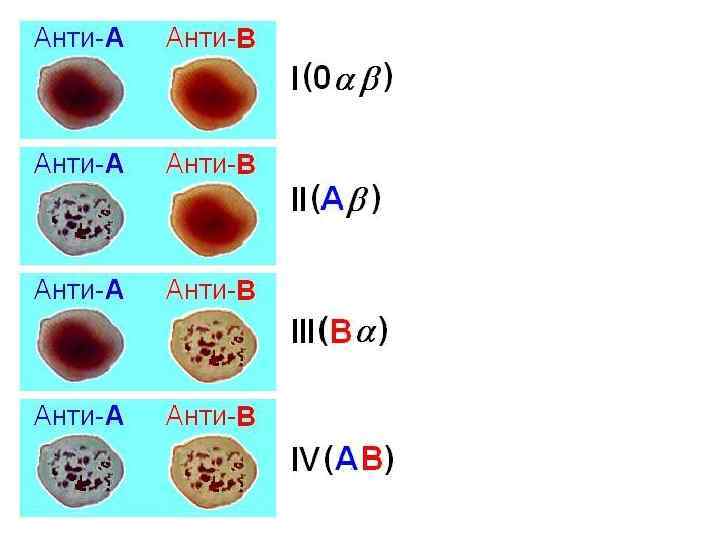

Вопрос 10 Система AB 0

Вопрос 10 Система AB 0

Стандартные сыворотки

Стандартные сыворотки